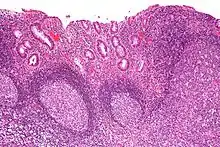

| Micrograph showing colonic-type mucosa with follicular lymphoid hyperplasia, as is seen in diversion colitis. H&E stain. | |

Diversion colitis is an inflammation of the colon which can occur as a complication of ileostomy or colostomy, where symptoms may occur between one month and three years following surgery.[1] It also occurs frequently in a neovagina created by colovaginoplasty, with varying delay after the original procedure.[2] Despite the presence of a variable degree of inflammation the most suggestive histological feature remains the prominent lymphoid aggregates.